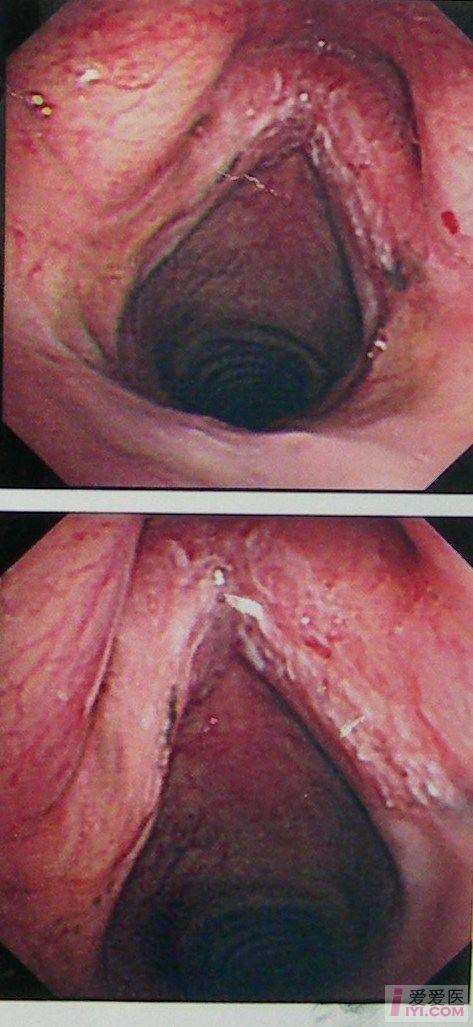

喉癌一临床表现与诊断

喉癌一及时发现及时诊断

喉癌(一)临床表现与诊断